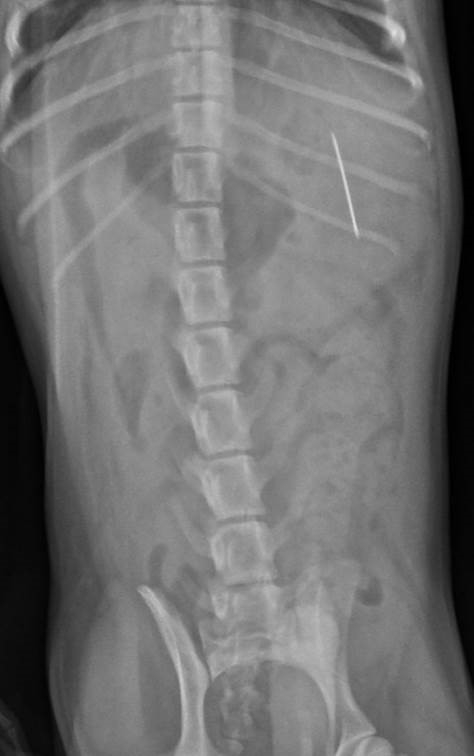

Cute little Doug the pug was taken to Wear Referrals, in Bradbury, County Durham, during lockdown after his worried owners had taken him to their local vet, who carried out x-rays that revealed the pet had swallowed a needle which had become lodged in his stomach.

She said: “Little Doug had somehow managed to swallow quite a large needle and attached thread, which obviously caused his owners considerable worry.

“We anaesthetised Doug on arrival and removed the needle and thread from his stomach via endoscopy, which is a flexible tube with a camera on the end and avoids the need for surgery.